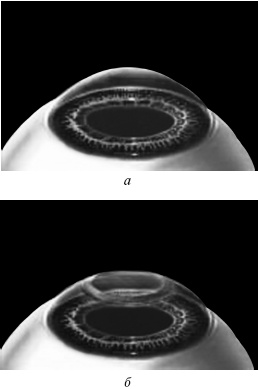

ЛАСИК – основной метод лазерной коррекции в мире в настоящее время. По большому счету, ФРК и ЛАСИК – единственные методы коррекции. Остальные методы являются либо модификациями ФРК и ЛАСИК, либо «компромиссом» между ними. Эпителий роговицы не трогают, так как он – залог быстрого заживления. Накладывают на глаз вакуумное кольцо – стальную присоску кольцевидной формы с присоединенной к нему трубочкой. Через трубочку из присоски отсасывается воздух, чтобы создать относительный вакуум. Отсасывает воздух главный аппарат для проведения ЛАСИКа – микрокератом. Это прибор размером с коробку из-под обуви. Его предназначение – срезание поверхностной крышки роговицы. К глазу присоединяют вакуумное кольцо, окружающее роговицу. Глаз четко фиксируется относительно кольца и сдвинуться с места может только с кольцом, в отверстие которого выступает купол роговицы. Затем к кольцу присоединяется головка микрокератома. Это второй инструмент микрокератома и соединяется с ним или шнуром, или тонким шлангом. Головка крепится на турбине, и вместе они имеют вид толстой шариковой ручки с обрубленным концом. Эту «ручку» хирург держит в правой руке, а вакуумное кольцо – в левой. Эта «ручка» нужна, чтобы сформировать крышечку роговицы. Внутри головки есть очень острое одноразовое лезвие. Турбина, соединенная с головкой, может двигать одноразовое лезвие туда-сюда, пилящими движениями. Можно резать роговицу, как хлеб, – пилящими движениями. И тут самое главное – скорость. Одноразовое лезвие делает 15000 пилящих движений в минуту. При такой скорости назвать это срезанием роговицы уже трудно, скорее это отслаивание верхних слоев. ![]() Рис. 3. Схема формирования роговичного лоскута с помощью микрокератома. Иллюстрация с сайта Международного лазерного центра www.optics.ru Итак, головка присоединяется к вакуумному кольцу и по специальным полозьям двигается над куполом роговицы (рис. 3). Срез, или отслаивание (называйте, как хотите), проводится не полностью, у крышечки (роговичного лоскута) остается маленький участок на периферии, соединяющий ее с роговицей (рис. 4). ![]() Рис. 4. Роговичный лоскут сформирован. Иллюстрация с сайта Международного лазерного центра www.optics.ru После формирования роговичного лоскута убирают инструменты микрокератома, затем шпателем откидывают его вбок (рис. 5). Обнажается роговичное ложе, то есть место, на котором лежал лоскут. Это верхние слои стромы роговицы. Ложе осушают тупфером и так же, как и при ФРК, настраивают лазер и испаряют несколько микрон вещества стромы (рис. 6). Потом промывают строму водой и шпателем укладывают лоскут на место. ![]() Рис. 5. Роговичный лоскут откинут в сторону. Иллюстрация с сайта Международного лазерного центра www.optics.ru ![]() Рис. 6. Луч эксимерного лазера испаряет на роговичном ложе несколько микрон стромы роговицы. Иллюстрация с сайта Международного лазерного центра www.optics.ru Стоит один раз моргнуть и лоскут скомкается и зрения не будет. Его бы пришить на место. Но швы деформируют роговицу. Все проще. Лоскут разглаживают мокрым тупфером, прижимая его ровненько к старому месту (рис. 7 и 8). Только место не старое, с роговичного ложа удалили несколько микрон в виде причудливой ямки (при коррекции близорукости). ![]() Рис. 7. При коррекции близорукости на роговичном ложе формируется «ямка». Иллюстрация с сайта Международного лазерного центра www.optics.ru ![]() Рис. 8. Роговичный лоскут укладывается на место. Иллюстрация с сайта Международного лазерного центра www.optics.ru Края роговичного лоскута осушают сухим тупфером. Влага, оставшаяся под лоскутом в ямке роговичного ложа, высасывается в тупфер. Лоскут притягивает к ложу, как вакуумную присоску. Вакуумом начали, вакуумом закончили. Ждем, когда закончится приживление лоскута к ложу. Эпителий цел и невредим. А значит, никаких болей. Около трех часов возможны слезотечение и светобоязнь. И все (рис. 9). ![]() Рис. 9. Форма роговицы до проведения коррекции (а) и после коррекции близорукости (б). Испарение нескольких микрон толщины роговицы привело к уменьшению ее кривизны в центре. Иллюстрация с сайта Международного лазерного центра www.optics.ru Хирурги о ЛАСИКе говорят: «90 % хирургии и 10 % долечивания». Лазерный субэпителиальный кератомилез (LASEK) Модификация ФРК. Чтобы укоротить неприятный послеоперационный период, эпителий, обработанный спиртовым или солевым раствором, отслаивают очень бережно, с помощью специальных инструментов, в виде цельного лоскута. А после испарения эксимерным лазером боуменовой мембраны и нужного количества слоев стромы этот эпителиальный лоскут укладывают обратно и, чтобы он не сместился, прижимают мягкой контактной линзой. Через 3–4 дня эпителий заживает, а благодаря линзе и даже еще не приживленному эпителиальному лоскуту боль и светобоязнь не беспокоят пациента с первых часов после коррекции, а зрение восстанавливается на пару недель быстрее, чем при ФРК. Также одной из модификаций ФРК является MAGEK. Основным отличием от ФРК является применение препарата Митомицин С (Mitomycin-С), который блокирует «слишком быстрое деление клеток» и снижает риск возникновения хейза. Эпи-ЛАСИК (Epi-LASIK) Нечто среднее между ЛАСИК и LASEK. Для отделения эпителия используются не спиртовой или солевой растворы, а специальный аппарат, очень похожий на микрокератом. Аппарат называется эпикератомом. Он отслаивает эпителий вместе с частью боуменовой мембраны в виде лоскута, похожего на лоскут при ЛАСИКе, только гораздо тоньше. После проведения коррекции лоскут также прижимают контактной линзой. Но не поврежденный химическим ожогом эпителиальный лоскут, да еще с остатками боуменовой мембраны, значительно сокращает период заживления и восстановления и снижает другие недостатки ФРК и LASEK, о которых будет сказано ниже. Рефракционный эксимерлазерный интростромальный кератомилез (РЭИК) |